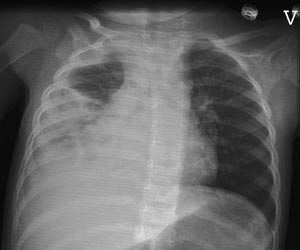

Pasient 1. En 21 måneder gammel tidligere frisk jente. Hun var forkjølet en uke før hun fikk akutt forverring med temperatur over 40 °C, stønnende respirasjon og generelt utslett og ble innlagt med mistanke om sepsis. Røntgen thorax viste et lite infiltrat basalt i venstre lunge og CRP var 100 mg/l. Hun ble utskrevet neste dag med pågående penicillinbehandling. Hun ble innlagt igjen fem dager senere etter at hun på nytt fikk høy feber. Røntgen thorax viste nå pleuravæske og infiltrat i høyre lunge (fig 4). CRP var 92 mg/l. Det ble tatt nasopharynxaspirat som var positiv for humant metapneumovirus, mens hun testet negativt for andre luftveisvirus. Antigenpåvisning og serologi for Bordetella pertussis, Chlamydia pneumoniae og Mycoplasma pneumoniae var negative. Hun hadde rikelig oppvekst av betahemolytiske streptokokker gruppe A og Streptococcus pneumoniae i halsprøve tatt ved første innleggelse. Blodkulturer var negative. Hun ble behandlet med cefotaksim intravenøst og ble utskrevet etter fem dager med amoxicillin. Først ved kontroll tre uker senere var pleuravæsken borte og jenta helt frisk.

Pasient 2. En sju år gammel jente med asthma bronchiale som ble innlagt med økende obstruktivitet etter en forkjølelse. Ved innleggelsen var oksygenmetningen 87 % og temperaturen 39,2 °C. Røntgen thorax viste uttalte bilaterale hilusnære infiltrater med atelektatisk preg og en stor atelektatisk fortetning i høyre lungetopp (fig 5). CRP var 13 mg/l. Det ble påvist humant metapneumovirus i nasopharynxaspirat. Hun testet negativt for andre luftveisvirus. På tross av hyppige inhalasjoner (adrenalin, salbutamol og budesonid) og metylprednisolon intravenøst, tilkom forverret hypoksi og økende infiltrater. Initial intravenøs penicillinbehandling ble skiftet til intravenøs erytromycin etter noen dager. Serologi for Mycoplasma pneumoniae var imidlertid negativ. Hun fikk oksygentilskudd i sju dager og var innlagt i 11 dager. Hun har ikke hatt akutt astmaforverring senere.